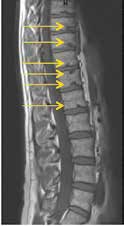

Mechanische Bedrängung der nervalen Strukturen

Kommt es bei einem Bandscheibenvorfall zu einer Nervenwurzelbedrängung, so kann durch entlastende und stellungskorrigierende Orthesen eine Beschwerdelinderung herbeigeführt werden. Die Industrie hat auf diese Pathologien mit „abrüstbaren“ Orthesen reagiert. Einer anfänglichen suffizienten Entlordosierung folgt eine Abrüstung der Orthese auf eine Bewegungslimitierung und anschließend Bewegungsfreigabe. Dieses Konzept ist auch mit dem aufgezeigten Vorgehen entsprechend dem Wolff’schen Gesetz stimmig und in sich logisch nachvollziehbar.

Dies ist aber nur dann sinnvoll, wenn eine sich ändernde Pathologie mit Besserungstendenz besteht. Nervenwurzelbedrängungen durch osteophytäre Ausziehungen etc. sind diesem Behandlungskonzept nicht zugänglich. Schmerzbehandlungen mit intraforaminellen Infiltrationen, Hiatus-sacralis-Infiltrationen oder auch nur Facetteninfiltrationen können in Kombination mit Orthesen in ihrer Effektivität gesteigert werden. Besteht hingegen bereits eine Spinalkanalstenose, so sind die Möglichkeiten der Orthesenversorgung ausgeschöpft (Abb. 7).